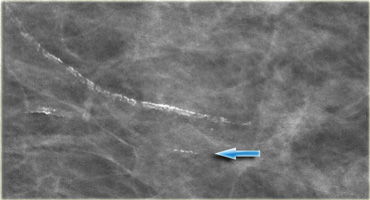

Vascular Calcifications

These are linear or form parallel tracks, that are usually clearly associated with blood vessels.

On the left typical vascular calcifications.

If only one side of a vessel is calcified (arrow), the calcification may simulate intraductal calcification, but usually the diagnosis is straight forward.